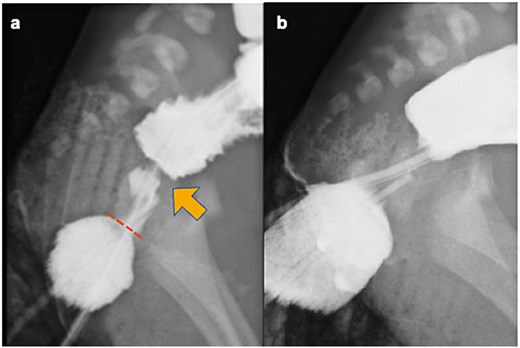

Contrast enema. (a) Preoperative contrast enema showing the rectal web (arrow) located approximately 1 cm from the anal verge (dotted line), with no fistula between the rectum and urethra. (b) Preoperative contrast enema revealing contrast medium stopping above the PC line.